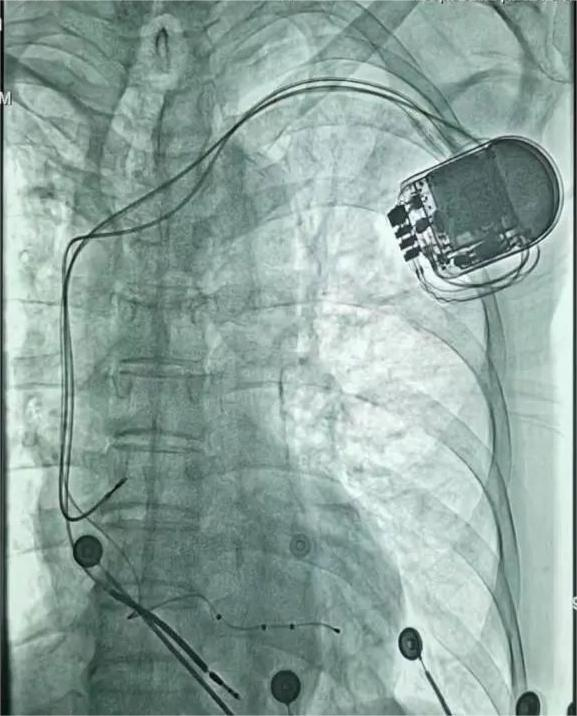

CRT-D植入中

3月30日为患者进行CRT-D植入术,经过充分的术前准备,王海雄博士、罗晋武主任医师、方艳平主任医师、苏新生主任医师、高淑华主任医师、武杰主治医师密切配合,穿刺患者左侧锁骨下静脉及腋静脉,经导管将三根电极分别植入患者的右心房、右心室和心中静脉,测试各参数达标后,在患者的胸壁胸大肌表面筋膜处植入了起搏器,仅在患者的胸壁处留有一处几厘米的创口,手术用时2小时。术后患者症状明显改善,心功能明显好转。目前,患者恢复良好。

CRT-D植入后